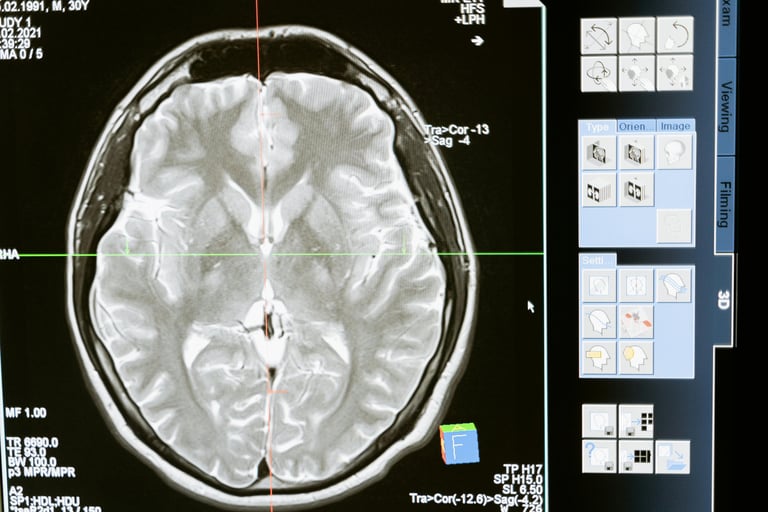

Brain Imaging Evidence in Gilbert’s Syndrome

A fascinating study from Japan used Magnetic Resonance Spectroscopy (MRS) to analyze brain chemistry in people with Gilbert’s Syndrome.

The researchers found reduced levels of myo-inositol, a marker of glial cell health, specifically astrocytes.